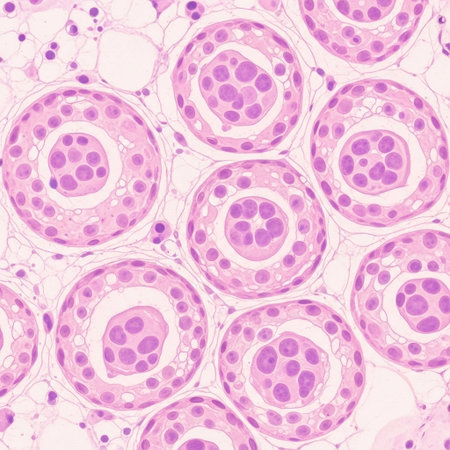

Histopathology of prostate gland hyperplasia, light micrograph, photo under microscope

Light micrograph of teratoma, a tumor made up of several different types of tissue, such as hair, teeth, muscle, or bone. Teratoma is typically found in the ovary, testicle, or coccyx

Photomicrograph showing histological features of benign prostatic hyperplasia. Enlarged prostate gland with nodular proliferation of glandular and stromal components.

Anatomy and Histological Ovary, Testis and Sperm human cells under microscope.

Photomicrograph showing histological features of benign prostatic hyperplasia. Enlarged prostate gland with nodular proliferation of glandular and stromal components.